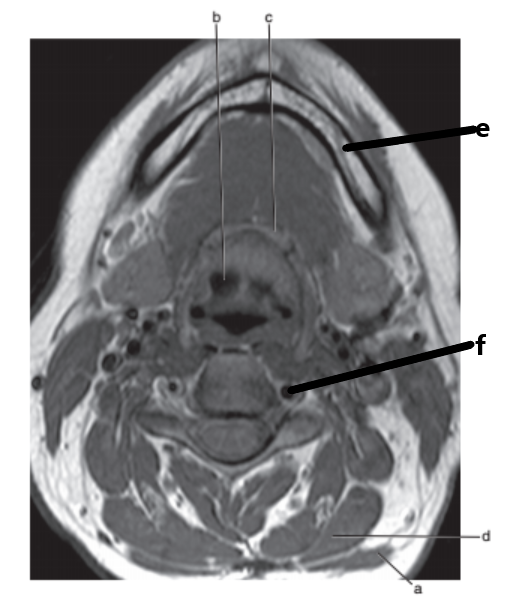

What anatomy is letter e ?

Nasopharynx

Sublingual gland

Mandible

Tongue

Parotid gland

What imaging plane is this ?

transverse

What anatomy is letter b ?

Epiglottis

What is letter d ?

Soft palate

Masseter muscle

What is letter e ?

What is # 3 ?

Brain stem

Submandibular gland

Hyoid bone